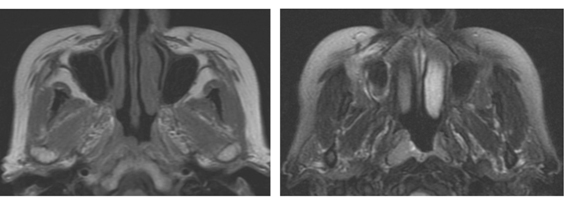

患者,男,53岁,发现鼻塞及右侧颈部包块、面部疼痛一个月余,查体左颈部有一质硬的包块。MRI如图所示:

3.本病最可能诊断为

4.以下关于本病描述不正确的是

正确答案:3.E;4.C